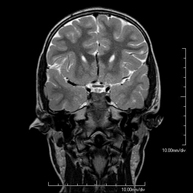

Magnetic Resonance Imaging

MRI under sedation

This non-invasive diagnostic procedure uses an electromagnetic field and radio waves (from a transmitter and receiver) to acquire high-definition anatomical images of any region of the body. It is a radiation-free procedure. It is performed under sedation with the assistance of an anaesthesia team. It is extremely useful in paediatric patients, who can often be difficult to examine because of artefacts caused by movements (infants, young children, etc., when clinically indicated).